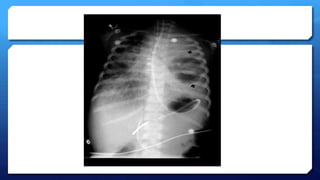

Evaluación radiológica:

 Confirmación del diagnóstico de neumonía

 Dos patrones

 Alveolar e intersticial. ¿viral o intersticial?

 Signos de neumonía bacteriana:

 50% casos  Infiltrados alveolares en parche o consolidación

lobar o de distribución subsegmentaria

 También se pueden encontrar en neumonías virales y

atípicas.

 Neumatoceles, abcesos pulmonares